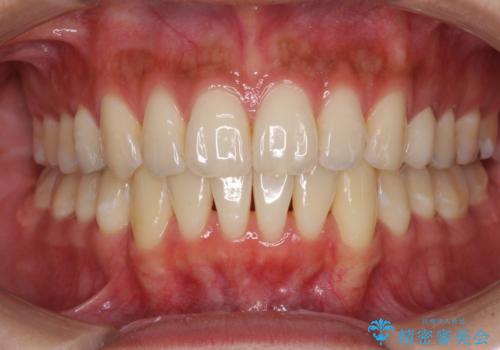

外観はもちろんのこと、隙間なく安心して咬むことのできる前歯となり、患者様には大変満足していただきました。